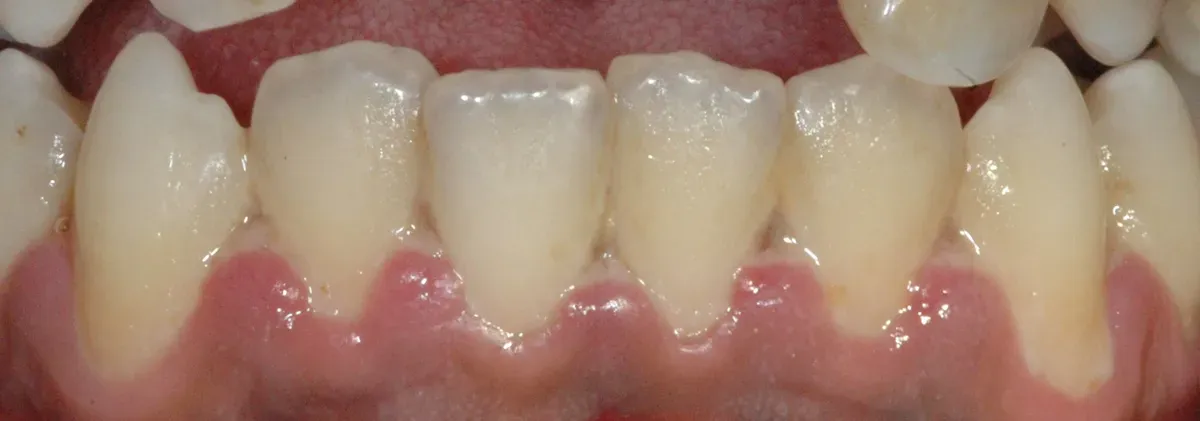

Guarda lo spazio tra un dente e l’altro. Quella piccola porzione di gengiva a forma di triangolo che riempie lo spazio si chiama papilla interdentale. Nella gengivite ulcero-necrotica, è proprio lì che inizia il problema.

Alcuni batteri detti “periopatogeni”, che normalmente possono vivere in bocca anche senza fare danni (patogeni opportunisti), hanno preso il sopravvento. Attaccano il tessuto, lo consumano. Si formano piccole ulcere coperte da una patina grigiastra. Il tessuto sano diventa tessuto morto. E le papille appaiono come “mozzate” (vedi immagine di copertina).

Immagine di copertina di dr.Mohamed HAMZE - personal practice in dental cabinet, Pubblico dominio, https://commons.wikimedia.org/w/index.php?curid=3378984